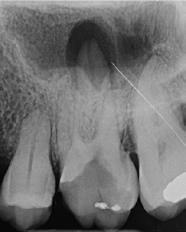

4. a ábra: A CBCT felvétel igazolja, hogy a jobb felső nagymetszőfog megfelelő pozícióba került. Az ínyszél lefutása kedvező, a fog gyökere körül elfogadható mennyiségű csontállomány ábrázolódik, valamint a gyökérfelszívódás mértéke sem túl kifejezett.

6 hónapon keresztül tartott. Ennek megfelelően a fog körül található szövetek a felszabadítás, valamint a havi kontrollok során 975 nm-es (több mint 25 J/cm2 energiasűrűség) és 660 nm-es hullámhosszúságú (12–18 J/cm2 energiasűrűség) lézersugarakkal is megvilágításra kerültek. Az impaktálódott fogat megközelítőleg 7 hónap alatt tudtuk megfelelő pozícióba mozgatni (3. ábra). Az orthodoncia kezelés aktív szakasza 18 hónapon keresztül tartott. A fogívek végső nivellálását és a fogak végleges pozícióba rendezését 0.018 × 0.025-ös acélívekkel végeztük.

A kezelés befejezésekor a páciens mosolya drámai mértékben javult, továbbá a frontfogak elhelyezkedése és az ínyszél lefutása is szemmel látható módon kedvezőbbé vált (4. ábra). A kezelés végén készült CBCT felvétel nem mutatta

csontfelszívódás jelenlétét, és csupán minimális mértékű gyökérfelszívódás bekövetkezését igazolta.

4. b ábra: A panoráma röntgenfelvétel is alátámasztja a CBCT felvételen látottakat. 4. c ábra: Az intraorális felvételen megfelelő fogpozíciók és kedvező ínyszéli lefutás ábrázolódik.